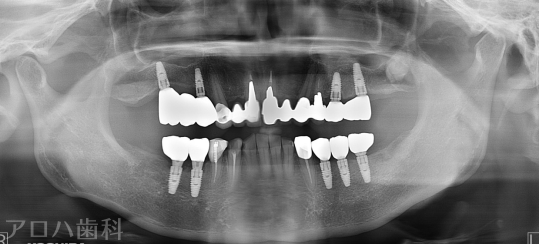

CASE01

初診時

治療終了後5年時

| 主訴 | 入れ歯をやり替えたい |

|---|---|

| 治療内容 | 上下顎とも状態が悪い歯を抜いて奥歯をインプラントで修復しました。 前歯は患者さまの希望のもとそのままにしています。 上顎は骨の高さが足りなかったため、【サイナスリフト】という特殊な手術を行い骨の高さを獲得しています。 術後経過もメインテナンスに通っていただいており、良好な状態を保っています。 |

| 治療期間 | 1年6ヶ月 |

| 治療費用 | 5,060,000円 |

| 費用詳細 | ・サイナスリフト(2か所) 660,000円 ・セデーション(静脈内鎮静法) 110,000円 ・TEC(仮歯) 220,000円 ・インプラント手術+アバットメント+上部構造(9歯) 3,960,000円 ・ポンティック(1歯) 110,000円 |